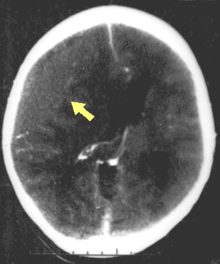

Hematomas, also focal lesions, are collections of blood in or around the brain that can result from hemorrhage.[3] Intracerebral hemorrhage, with bleeding in the brain tissue itself, is an intra-axial lesion. Extra-axial lesions include epidural hematoma, subdural hematoma, subarachnoid hemorrhage, and intraventricular hemorrhage.[31] Epidural hematoma involves bleeding into the area between the skull and the dura mater, the outermost of the three membranes surrounding the brain.[3] In subdural hematoma, bleeding occurs between the dura and the arachnoid mater.[15] Subarachnoid hemorrhage involves bleeding into the space between the arachnoid membrane and the pia mater.[15] Intraventricular hemorrhage occurs when there is bleeding in the ventricles.[31]

Surgery can be performed on mass lesions or to eliminate objects that have penetrated the brain. Mass lesions such as contusions or hematomas causing a significant mass effect (shift of intracranial structures) are considered emergencies and are removed surgically.[15] For intracranial hematomas, the collected blood may be removed using suction or forceps or it may be floated off with water.[15] Surgeons look for hemorrhaging blood vessels and seek to control bleeding.[15] In penetrating brain injury, damaged tissue is surgically debrided, and craniotomy may be needed.[15] Craniotomy, in which part of the skull is removed, may be needed to remove pieces of fractured skull or objects embedded in the brain.[99] Decompressive craniectomy (DC) is performed routinely in the very short period following TBI during operations to treat hematomas; part of the skull is removed temporarily (primary DC).[100] DC performed hours or days after TBI in order to control high intracranial pressures (secondary DC) has not been shown to improve outcome in some trials and may be associated with severe side-effects.[2][100]